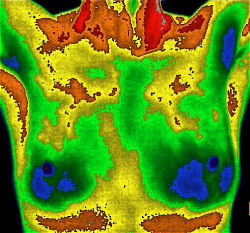

Breast Thermography at Pacific Naturopathic

ThermographyRestore your Peace of Mind